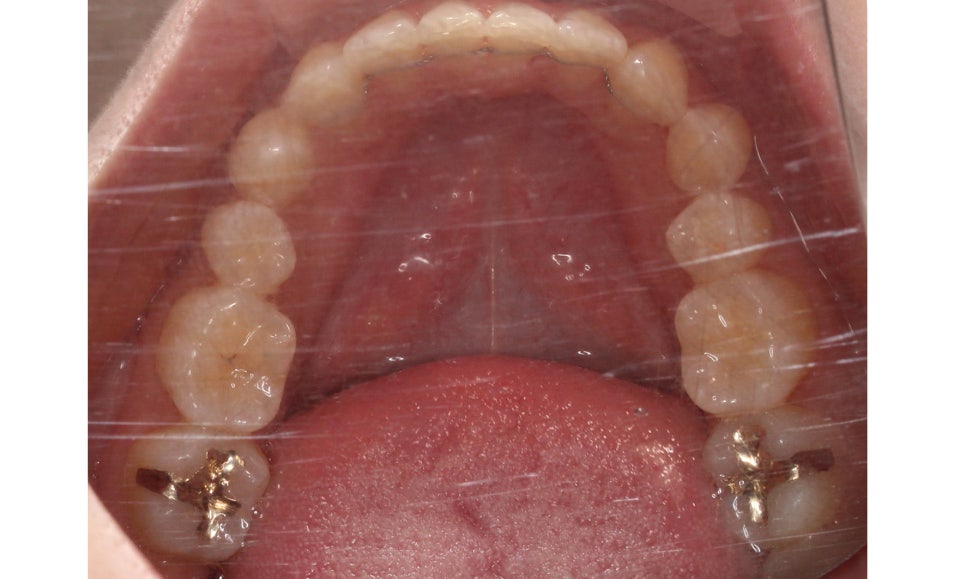

하악은 상악에 비해 심하게 틀어지진 않았지만

전치부의 치아들이 회전된 모습이 나타나기 때문에

이를 바르게 교정하여 전치부의 심미성을

보완하도록 하였습니다.

하악 또한 상악과 같이 전치부에서

발견되던 crowding이 사라졌고

치열이 가지런하게 바뀐 모습을 확인할 수 있는데요,